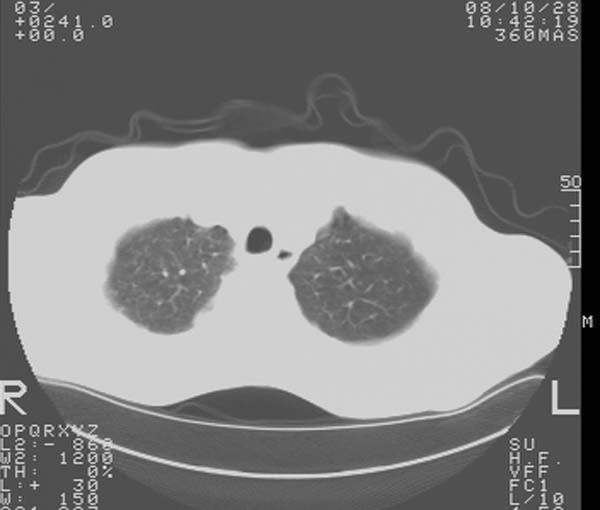

m,65y。半年前发现颈小结节,逐渐增多增大,现双侧耳后、颌下及颈部表浅淋巴肿大。胸片示双肺门增大。外院曾穿刺诊断为淋巴结核。在我科作胸腹部ct,我们觉得外院病检有误。现将图像上传请战友讨论。

纵隔内及腹膜后广泛淋巴结肿大,脾大,肝内似可见低密度影,结合病史半年前发现颈小结节,逐渐增多增大,现双侧耳后、颌下及颈部表浅淋巴肿大。考虑淋巴瘤。

纵隔,双肺门腹膜后多发淋巴结重大,非融合,肝脾轻度肿大,双肺野弥漫性小结节;考虑淋巴瘤,结节病可能性

纵隔内,双肺门、腋窝及腹膜后多发肿大淋巴结影,肺内小结节影,肝脾体积增大,支持淋巴瘤。肝内多发低密度影,考虑小囊肿。